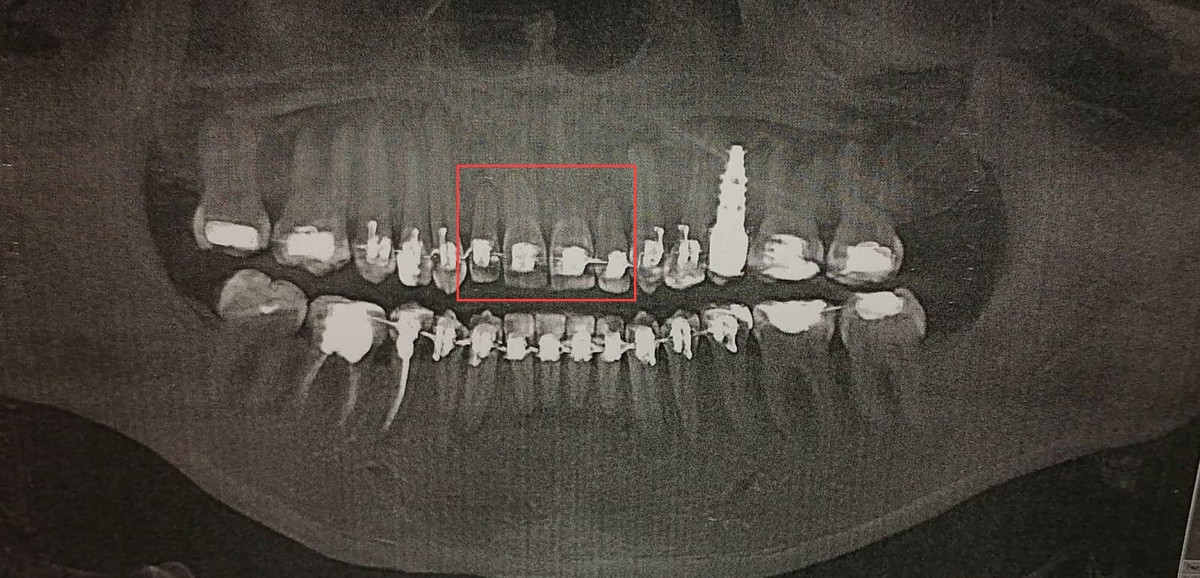

— Я говорю: «Давайте сделаем снимок, у меня там что-то болит». Сделала, приношу ему, а он говорит: «Все, брекеты больше носить нельзя, потому что у тебя корни зубов 12, 11, 21, 22 (четыре передних верхних зуба. — Прим. Onlíner) рассосались, там уже почти нет корней».

Пациентка утверждает, что это был первый раз за все годы лечения, когда ее направили на 3D-снимок. И он сразу же показал резорбцию, то есть разрушение костной ткани. Спустя несколько месяцев с верхней челюсти, где обнаружились проблемы, брекеты девушке сняли (это случилось в августе 2024 года). Юлия говорит, что результат длительного лечения ее расстроил, но обнаружила она это уже дома, не в поликлинике.

Результат семилетнего лечения. Юлия обращает внимание на щель между верхней и нижней челюстями

Эксперты вновь обратили внимание на то, что в амбулаторную карту не вносились все записи о приемах пациентки. С октября 2017 по сентябрь 2021 года лечение шло «в соответствии с установленным диагнозом, состоянием пациентки и требованиями клинического протокола». Далее в карте есть запись о завершении плана лечения от 3 сентября 2021 года. При этом ничего не говорится о снятии брекетов и установке ретейнеров (что является необходимым этапом для удержания зубов в нужном положении).

С января 2023 по сентябрь 2024 года лечение брекетами официально продолжилось, но диагноз не устанавливался, отмечают эксперты. Рентгеновские исследования не проводились, хотя они могли бы предупредить развитие осложнений — таковы выводы комиссии. Эксперты отмечают, что после снятия брекет-системы в сентябре 2024 года девушке был изготовлен ретенционный аппарат — капа, но для его установки пациентка не явилась. Таким образом, лечение не окончено по «не зависящим от врача-стоматолога-ортодонта причинам».

Тем не менее комиссия считает, что неполный объем ортодонтического лечения в первые четыре года и «бесконтрольное дальнейшее его продолжение» повлияли на состояние здоровья пациентки и вызвали осложнения.

Таким образом, эксперты пришли к выводу, что «стоматологическая услуга не соответствует медицинским стандартам и правилам».